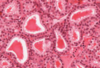

Which stain has been used in the image above to demonstrate the microvillous brush boarder?

- Alcian blue

- H+E

- Iron haematoxylin

- PAS

- Perls

- PAS. These are intestinal villi stained by the PAS procedure (magenta pink stain) and with haematoxylin (blue stain). The wine-glass shaped goblet cells stain dark pink as does the brush border. The nuclei of the columnar epithelial cells stain blue.